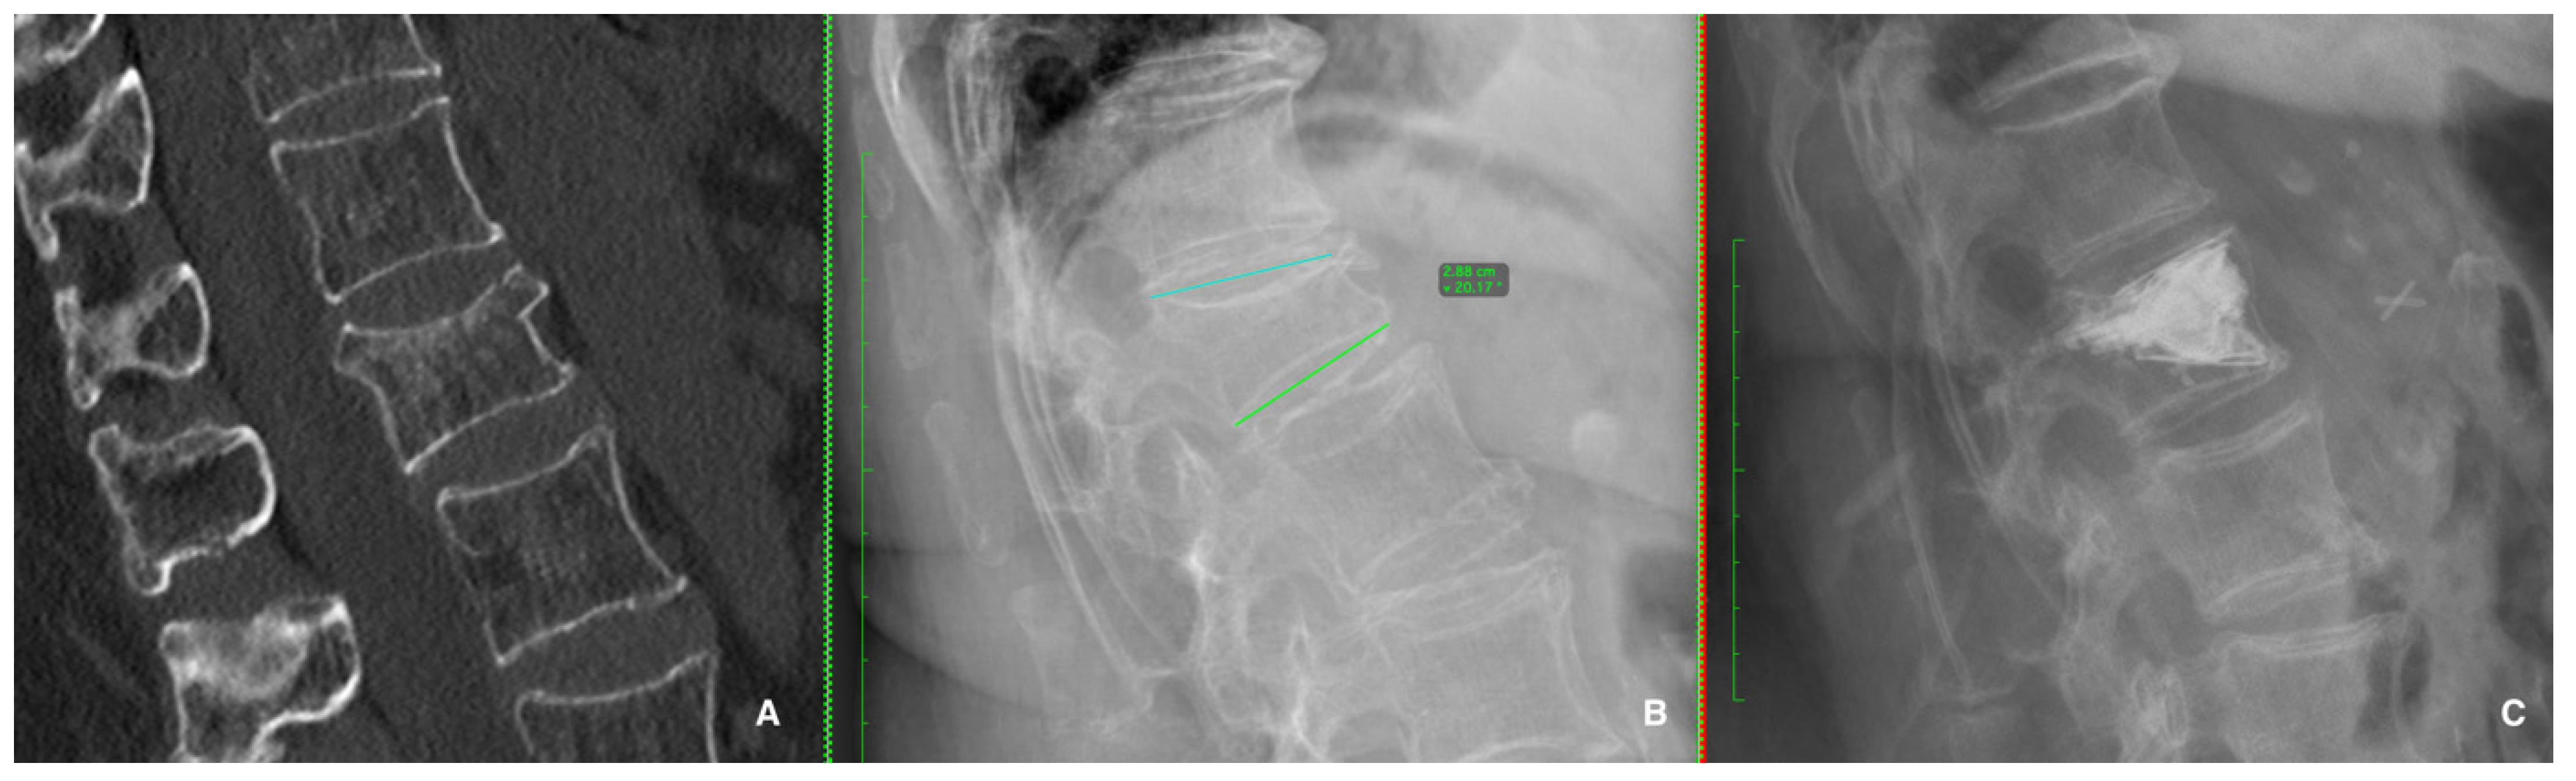

- Diacinti, D.; Guglielmi, G. Vertebral morphometry. Radiol. Clin. N. Am. 2010, 48, 561–575. [Google Scholar] [CrossRef]

- Diacinti, D.; Pisani, D.; Del Fiacco, R.; Francucci, C.M.; Fiore, C.E.; Frediani, B.; Barone, A.; Bartalena, T.; Cattaruzza, M.S.; Guglielmi, G.; et al. Vertebral morphometry by X-ray absorptiometry: Which reference data for vertebral heights? Bone 2011, 49, 526–536. [Google Scholar] [CrossRef]

- Sugita, M.; Watanabe, N.; Mikami, Y.; Hase, H.; Kubo, T. Classification of vertebral compression fractures in the osteopo-rotic spine. J. Spinal Disord. Tech. 2005, 18, 376–381. [Google Scholar] [CrossRef] [PubMed]

- Genant, H.K.; Wu, C.Y.; Van Kuijk, C.; Nevitt, M.C. Vertebral fracture assessment using a semiquantitative technique. J. Bone Min. Res. 1993, 8, 1137–1148. [Google Scholar] [CrossRef]